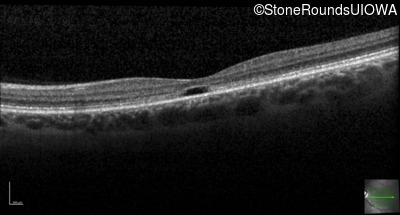

Optical Coherence Tomography - Left - 20/40

Exemplar / OCT Stack